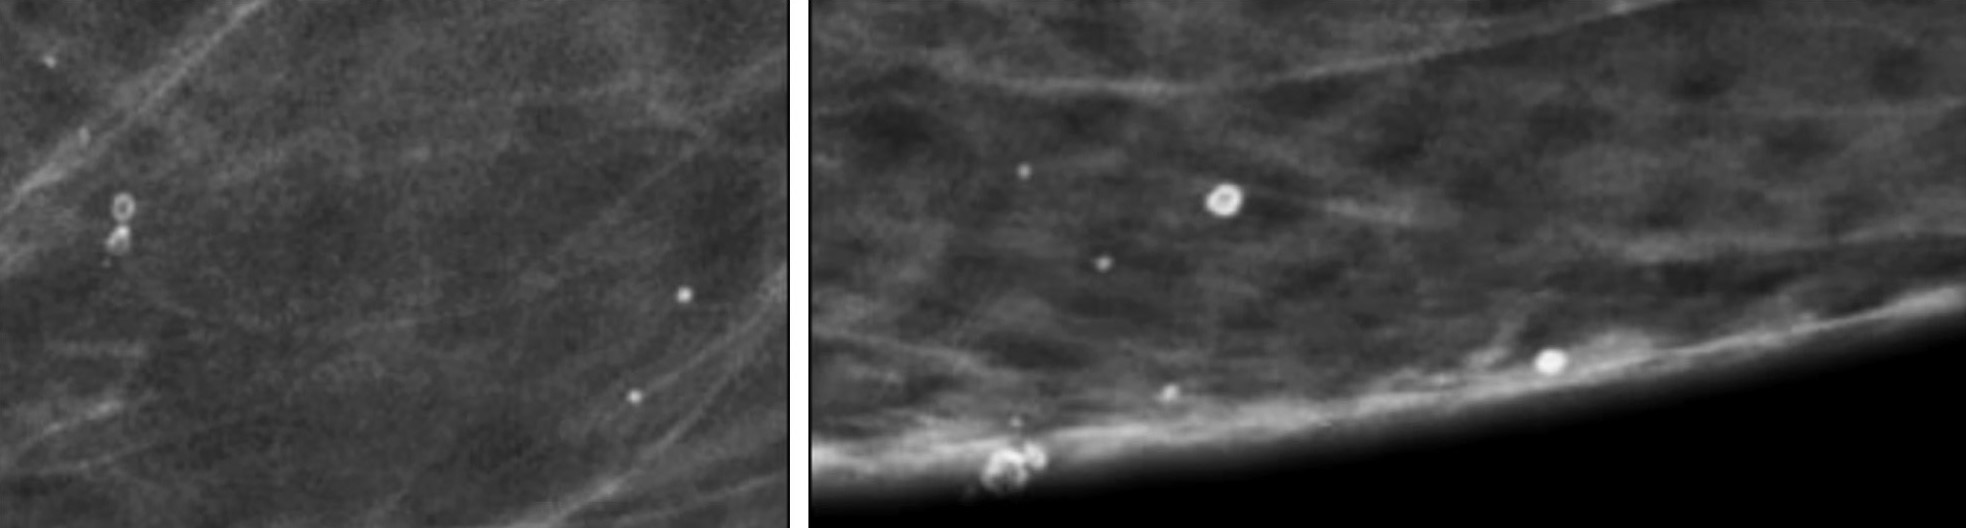

Внутрикожные кальцинаты локализованы преимущественно в дерме и являются результатом обызвествления протоков сальных желез. Чаще всего локализуются группами, имеют кольцевидную или точечную форму (Рис.3).

Для фиброзно-кистозных изменений характерны кальцинаты по типу Weddell. Как правило, они имеют квадратную, треугольную или трапецивидную форму (Рис.4).

Округлые кальцинаты с просветлением в центре, кальцинаты по типу «яичной скорлупы» характерны для обызвествления макро- и микрокист (Рис.5).

Кроме того, для обызвествления мелких кист молочной железы характерны кальцинаты по типу «молочка кальция». Образуются в результате седиментации кальция в структуре кисты и имеют форму чашечки или полумесяца в боковой проекции (Рис.6).

Глыбчатые микрокальцинаты с множественными просветами внутри характерны для обызвествленных папиллом (Рис.8).

При инфильтрации перидуктальной стромы плазматическими клетками и пролиферации клеток базальной мембраны протоков образуются линейные, стержневидные кальцинаты ориентированные по ходу протоков. Такая картина патогномонична для перенесенного плазмоклеточного мастита (Рис.9).